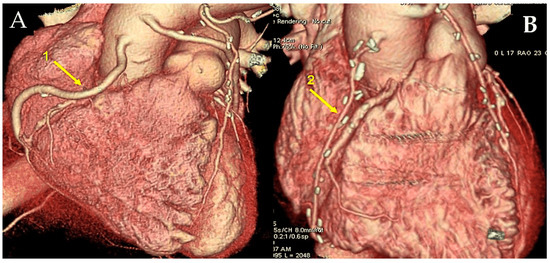

The most common type of angiographic failure observed in radial artery grafts is total obstruction, although a string-like appearance has also been documented. In rare instances, a localised stenosis of the radial artery graft has been identified [151]. Our own experience, spanning two decades, indicates that 6% of RA grafts exhibited stenosis on angiographic controls [151]. In some cases, stenosis was identified at either the proximal or distal anastomosis. In such instances, the potential culprits included a flawed surgical technique or intimal hyperplasia. In more frequent instances, stenosis affected the bodily region of the RA graft, thereby posing challenging pathophysiological concerns. It can often prove problematic to definitively exclude a spasm that is refractory to in situ vasodilators. If identified at an early stage following surgery, the stenosis can be treated with balloon dilation without the need for stenting [151]. If the stenosis is not identified in a timely manner, it is typically of an organic nature. It is possible that some narrowings existed prior to surgery involving the radial artery at the forearm. The development of RA stenosis may be attributable to the presence of an atheromatous plaque that had not been identified at the time of the initial surgical procedure. An additional possibility is that it is associated with fibrosis resulting from arterial trauma caused by inadequate harvesting techniques or prior intravascular procedures. It has been demonstrated that transradial angiography often results in intimal damage and/or medial dissection [152]. In certain instances, the stenosis of the radial artery was identified as a subsequent occurrence, as evidenced by instances where the graft was found to be intact in previous angiograms [151]. It seems plausible to suggest that these vessels may have been the focus of a preceding minor perivascular injury, which subsequently developed into a clinically significant flow-limiting stenosis. It can be reasonably deduced that the occurrence of RA graft stenosis may be prevented by the implementation of a systematic preoperative echo-doppler screening process, coupled with the deliberate preclusion of all calcified RAs and prior interventionally treated conduits. It is possible to safely treat RA graft stenoses by means of PCI and stenting, with the result being durable [151,153]. In regard to percutaneous interventions for venous graft disease, a significant challenge persists due to the high incidence of periprocedural morbidity associated with embolic complications from atherothrombotic detritus (Figure 6) [154].